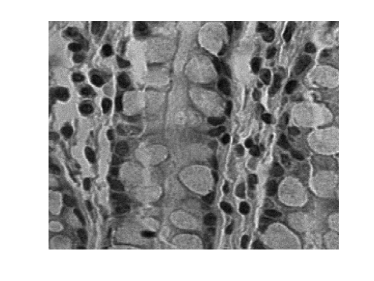

Hyper-spectral images are also used in medical applications such as detection of tissue anomalies. In this case a hyper-spectral microscope is used to capture hyper-spectral images of tissue samples. These images are analyzed in order to detect benign and malignant tumors [144, 145, 56]. Figure 1.3 shows two wavelengths of a hyper-spectral microscope-generated image of a human colon tissue. A more comprehensive introduction on hyper-spectral imagery, can be found in Chapter 5.

![]() |